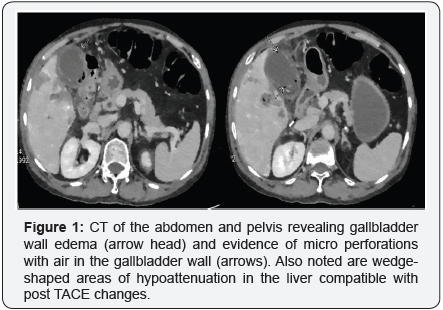

\Over the next 2 days his pain persisted and was accompanied by intermittent “shakes” and a low grade fever at 38 degrees. He was tachycardic to 110 beats per minute but remained normotensive. He had a tender right upper quadrant with a negative murphy’s sign, no rebound and no guarding. Laboratory markers were remarkable for a white cell count of 22.2 x 103cells/μL, alanine and aspartate transaminase peaking at 1190 U/L and 877 U/L respectively, alkaline phosphatase of 180 U/L and bilirubin of 1.1 mg/dL. The INR and hemoglobin levels remained stable. A liver ultrasound revealed changes related to the TACE procedure but also a moderately distended gallbladder with non-dependent air and wall edema. A CT scan of the abdomen and pelvis revealed an infracted gallbladder with emphysematous cholecystitis and small areas of gallbladder wall perforation (Figure 1).